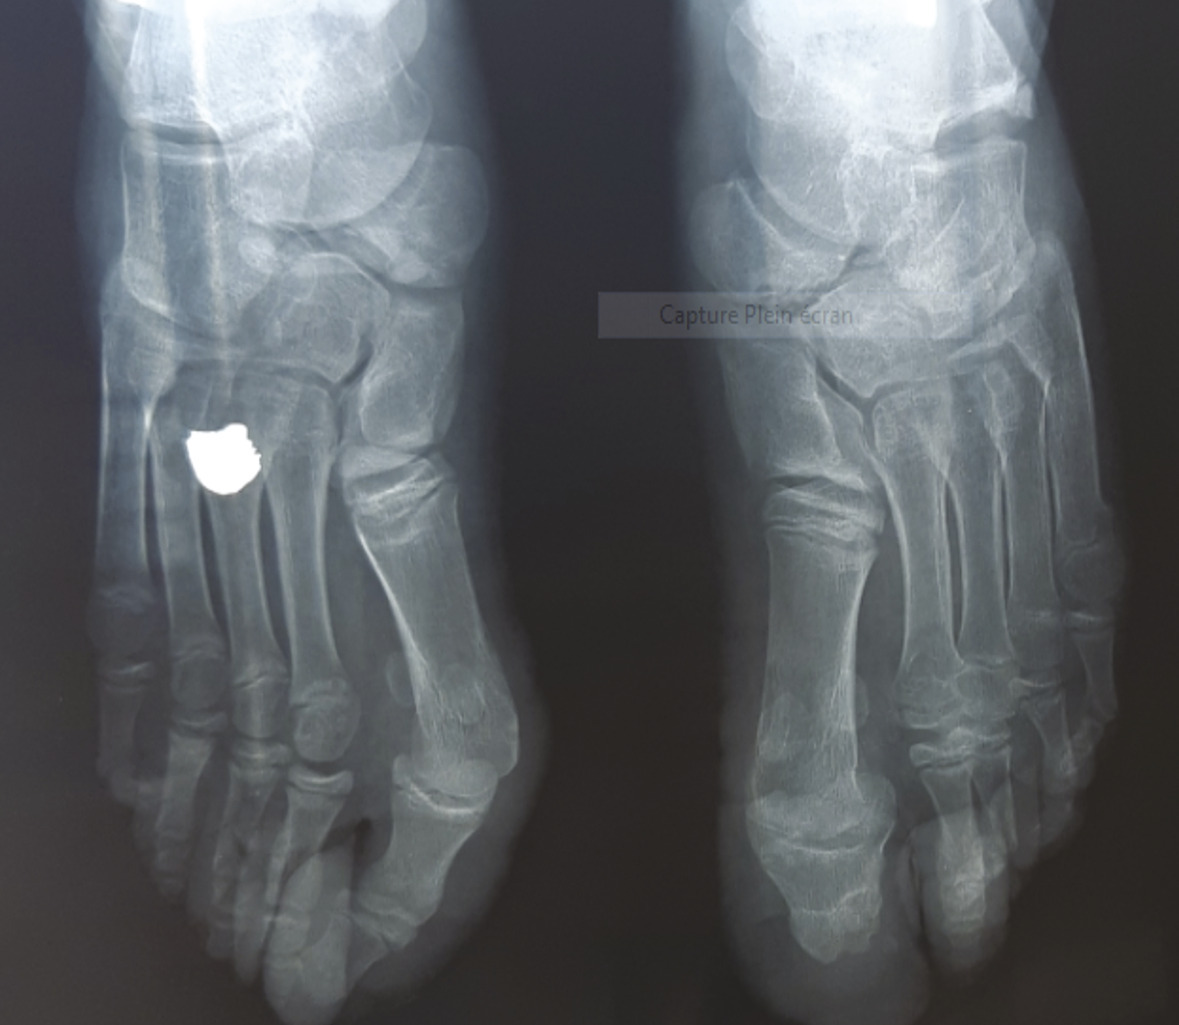

Les explorations radiographiques des avant-pieds montrent des lésions osseuses à type d’érosions, de déminéralisation et de reconstruction des petits os du pied en plus de la subluxation des premières métacarpo-phalangiennes en bilatéral (fig. 2 ).

Les explorations radiographiques des avant-pieds montrent des lésions osseuses à type d’érosions, de déminéralisation et de reconstruction des petits os du pied en plus de la subluxation des premières métacarpo-phalangiennes en bilatéral (

L’exploration radiographique au niveau des extrémités montre des images d’érosion et de lyse des os du tarse et des phalanges, aussi bien que des images de subluxation articulaire.